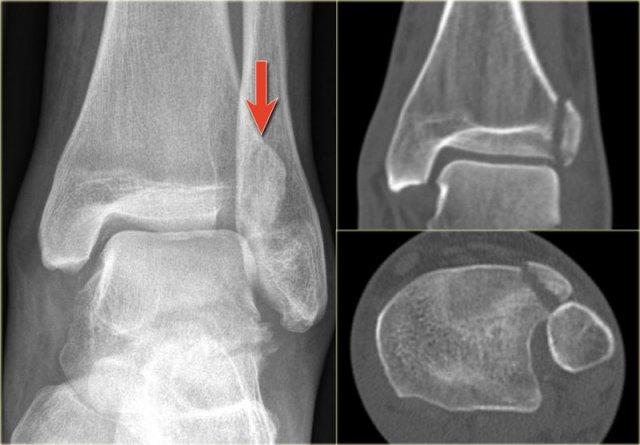

Trong một số trường hợp, gãy mắt cá sau hầu như không nhìn thấy hoặc không thể phát hiện trên phim X-quang và chỉ có thể thấy được trên CT.

Hãy đọc phim X-quang trước, sau đó tiếp tục với hình ảnh CT.

Lưu ý…. có hai đường gãy.

CT cho thấy hình ảnh bong điểm bám tertius tại vị trí bám của dây chằng chày mác sau (mũi tên đỏ).

Sự tương hợp của các mảnh gãy hoàn hảo đến mức không thể nhìn thấy đường gãy trên phim X-quang.

Có thể đường gãy được thấy trên tư thế thẳng (AP) như được chỉ ra bởi các mũi tên đỏ, nhưng điều này còn chưa chắc chắn.

Lưu ý rằng còn có thêm một tổn thương bong điểm bám tại vị trí bám của dây chằng chày mác trước vào xương chày, tức là gãy Tillaux.

Sự kết hợp các dấu hiệu này cho thấy cổ chân không vững.

Cần phải đặt vít cố định khớp chày mác.